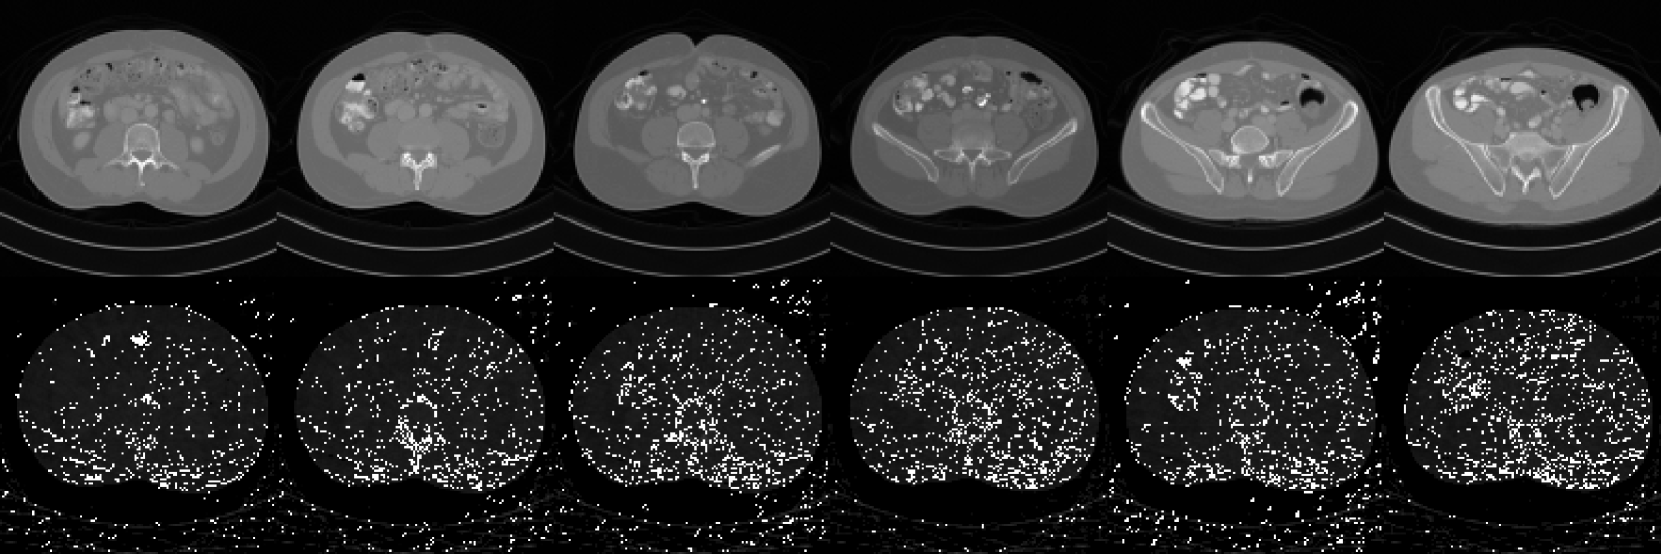

Quantitative results are provided in Table 1, 3D Gaussian achieves superior performance in most cases, usually by a large margin. A visual comparison between images reconstructed using NeRP and 3D Gaussians is shown in Fig. 3. Compared to NeRP, reconstructing images with 3D Gaussians provides cleaner results in empty regions and better high-frequency details like the airways.

We further explore factors that affect the reconstruction quality with 3D Gaussians. This includes examining the number of Gaussians involved and their initialization method, as well as providing evidence of the efficacy of adaptive density control.

To understand the number of Gaussians needed to represent an image volume, we turn off the adaptive density control during training, which brings perturbation to the number of Gaussians, and use 10K, 50K, 150K, 300K, 400K, 600K Gaussians to represent a volume. The results are shown in Fig. 3(b) and Fig. 3(c), respectively. The reconstruction performance generally improves with the increase in number of Gaussians used. However, an overly large number of Gaussians can lead to a degraded quality, which may be attributed to the low quality of initialized centers with the increase in number of selected points.

3.3.2 Initialization of Gaussians

We compare our initialization from FBP-reconstructed image strategy with uniform initialization. For uniform initialization, we use the same threshold to filter the air region and initialize the center of Gaussians uniformly across the foreground region, and all Gaussisans are initialized with the same standard deviation and intensity. Quantitative results are listed in Table 1, and visualization is provided in Fig. 3. Initialization from FBP-reconstructed images consistently outperforms uniform initialization by a large margin, suggesting the importance of starting with an informed initial placement of Gaussians.

3.3.3 Effectiveness of Adaptive density control

In our main experiment, we initialize an image with 150K Gaussians and set the upper bound to 400K. Comparisons of reconstruction with and without adaptive density control are provided in Fig. 3(b) and Fig. 3(c). Adaptive density control greatly improves the final reconstruction performance. Moreover, analyzing the correlation between number of Gaussians employed and reconstruction quality reveals that each substantial increase in number of Gaussians corresponds to a temporary drop in reconstruction quality, then recovery and improvement, as depicted in Fig. 3(a). This suggests adaptive density control helps place the Gaussians in a better place compared with solely based on optimization.